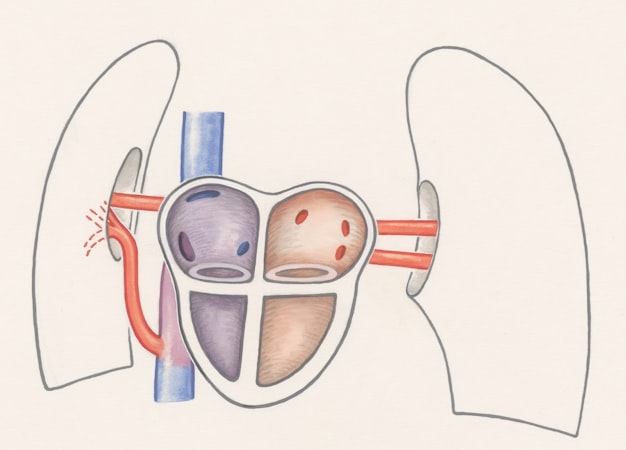

- إصلاح الدوالي (دوالي الخصية) قد يحسن العدد والحركة عند بعض الرجال.

العلاج الجراحي يعالج مشكلة في البنية (دوالي) بينما العلاج الهرموني يعالج خللاً في الغدد أو الهرمونات.

تفصيل: اختيار العلاج يعتمد على الفحوصات (صورةٍ بالموجات فوق الصوتية واختبارات هرمونية).